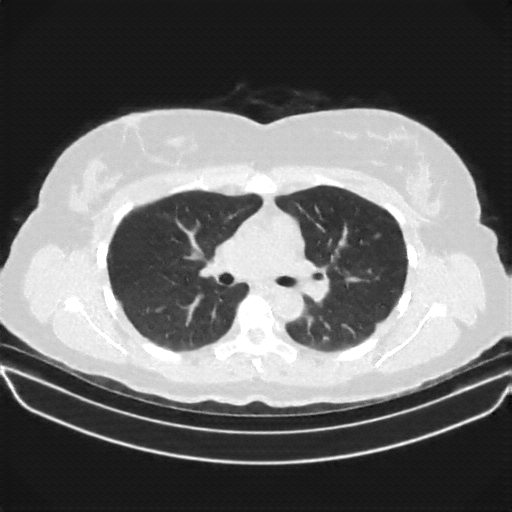

Original VENOUS CT scan

Full window (WL 1023.5, WW 4095 β†’ Low βˆ’1024, High +3071)

Actual HU range: [-1024.0, 1298.0]

Lung window (WL -600, WW 1500 β†’ Low βˆ’1350, High +150)

Actual HU range: [-1024.0, 150.0]

Mediastinum window (WL 40, WW 400 β†’ Low βˆ’160, High +240)

Actual HU range: [-160.0, 240.0]